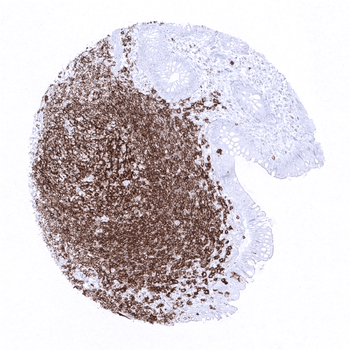

In the tonsil, many lymphocytes stain positive while the surface epithelium is CD20 negative.